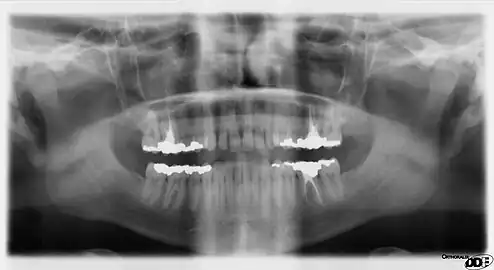

![]() A dental panoramic radiograph, showing the maxilla and mandible, all the teeth including the "wisdom teeth," the frontal and maxillary sinuses, the nasal cavity and the temporomandibular joint and other near by head and neck anatomy. | |

A panoramic radiograph is a panoramic scanning dental X-ray of the upper and lower jaw. It shows a two-dimensional view of a half-circle from ear to ear. Panoramic radiography is a form of focal plane tomography; thus, images of multiple planes are taken to make up the composite panoramic image, where the maxilla and mandible are in the focal trough and the structures that are superficial and deep to the trough are blurred.